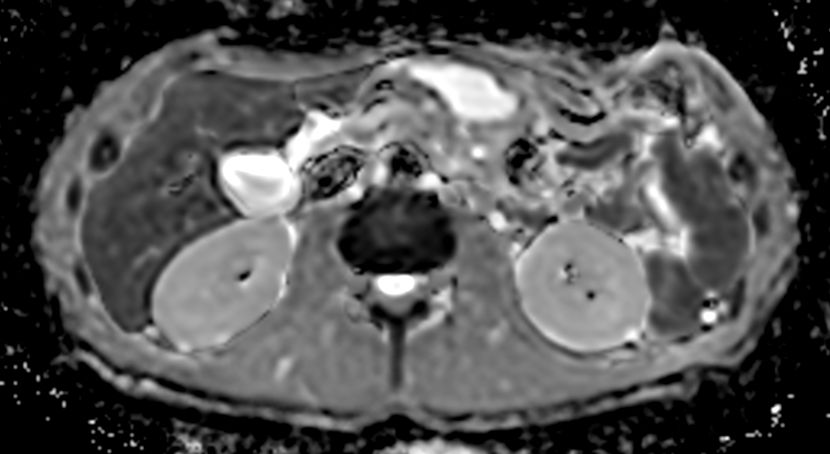

Axial DWI b10003mm slices

-

Axial DWI b503mm slices

Axial DWI b6003mm slices

Axial DWI ADC3mm slices

Axial DWI b504mm slices

Axial DWI b6004mm slices

Axial DWI ADC4mm slices